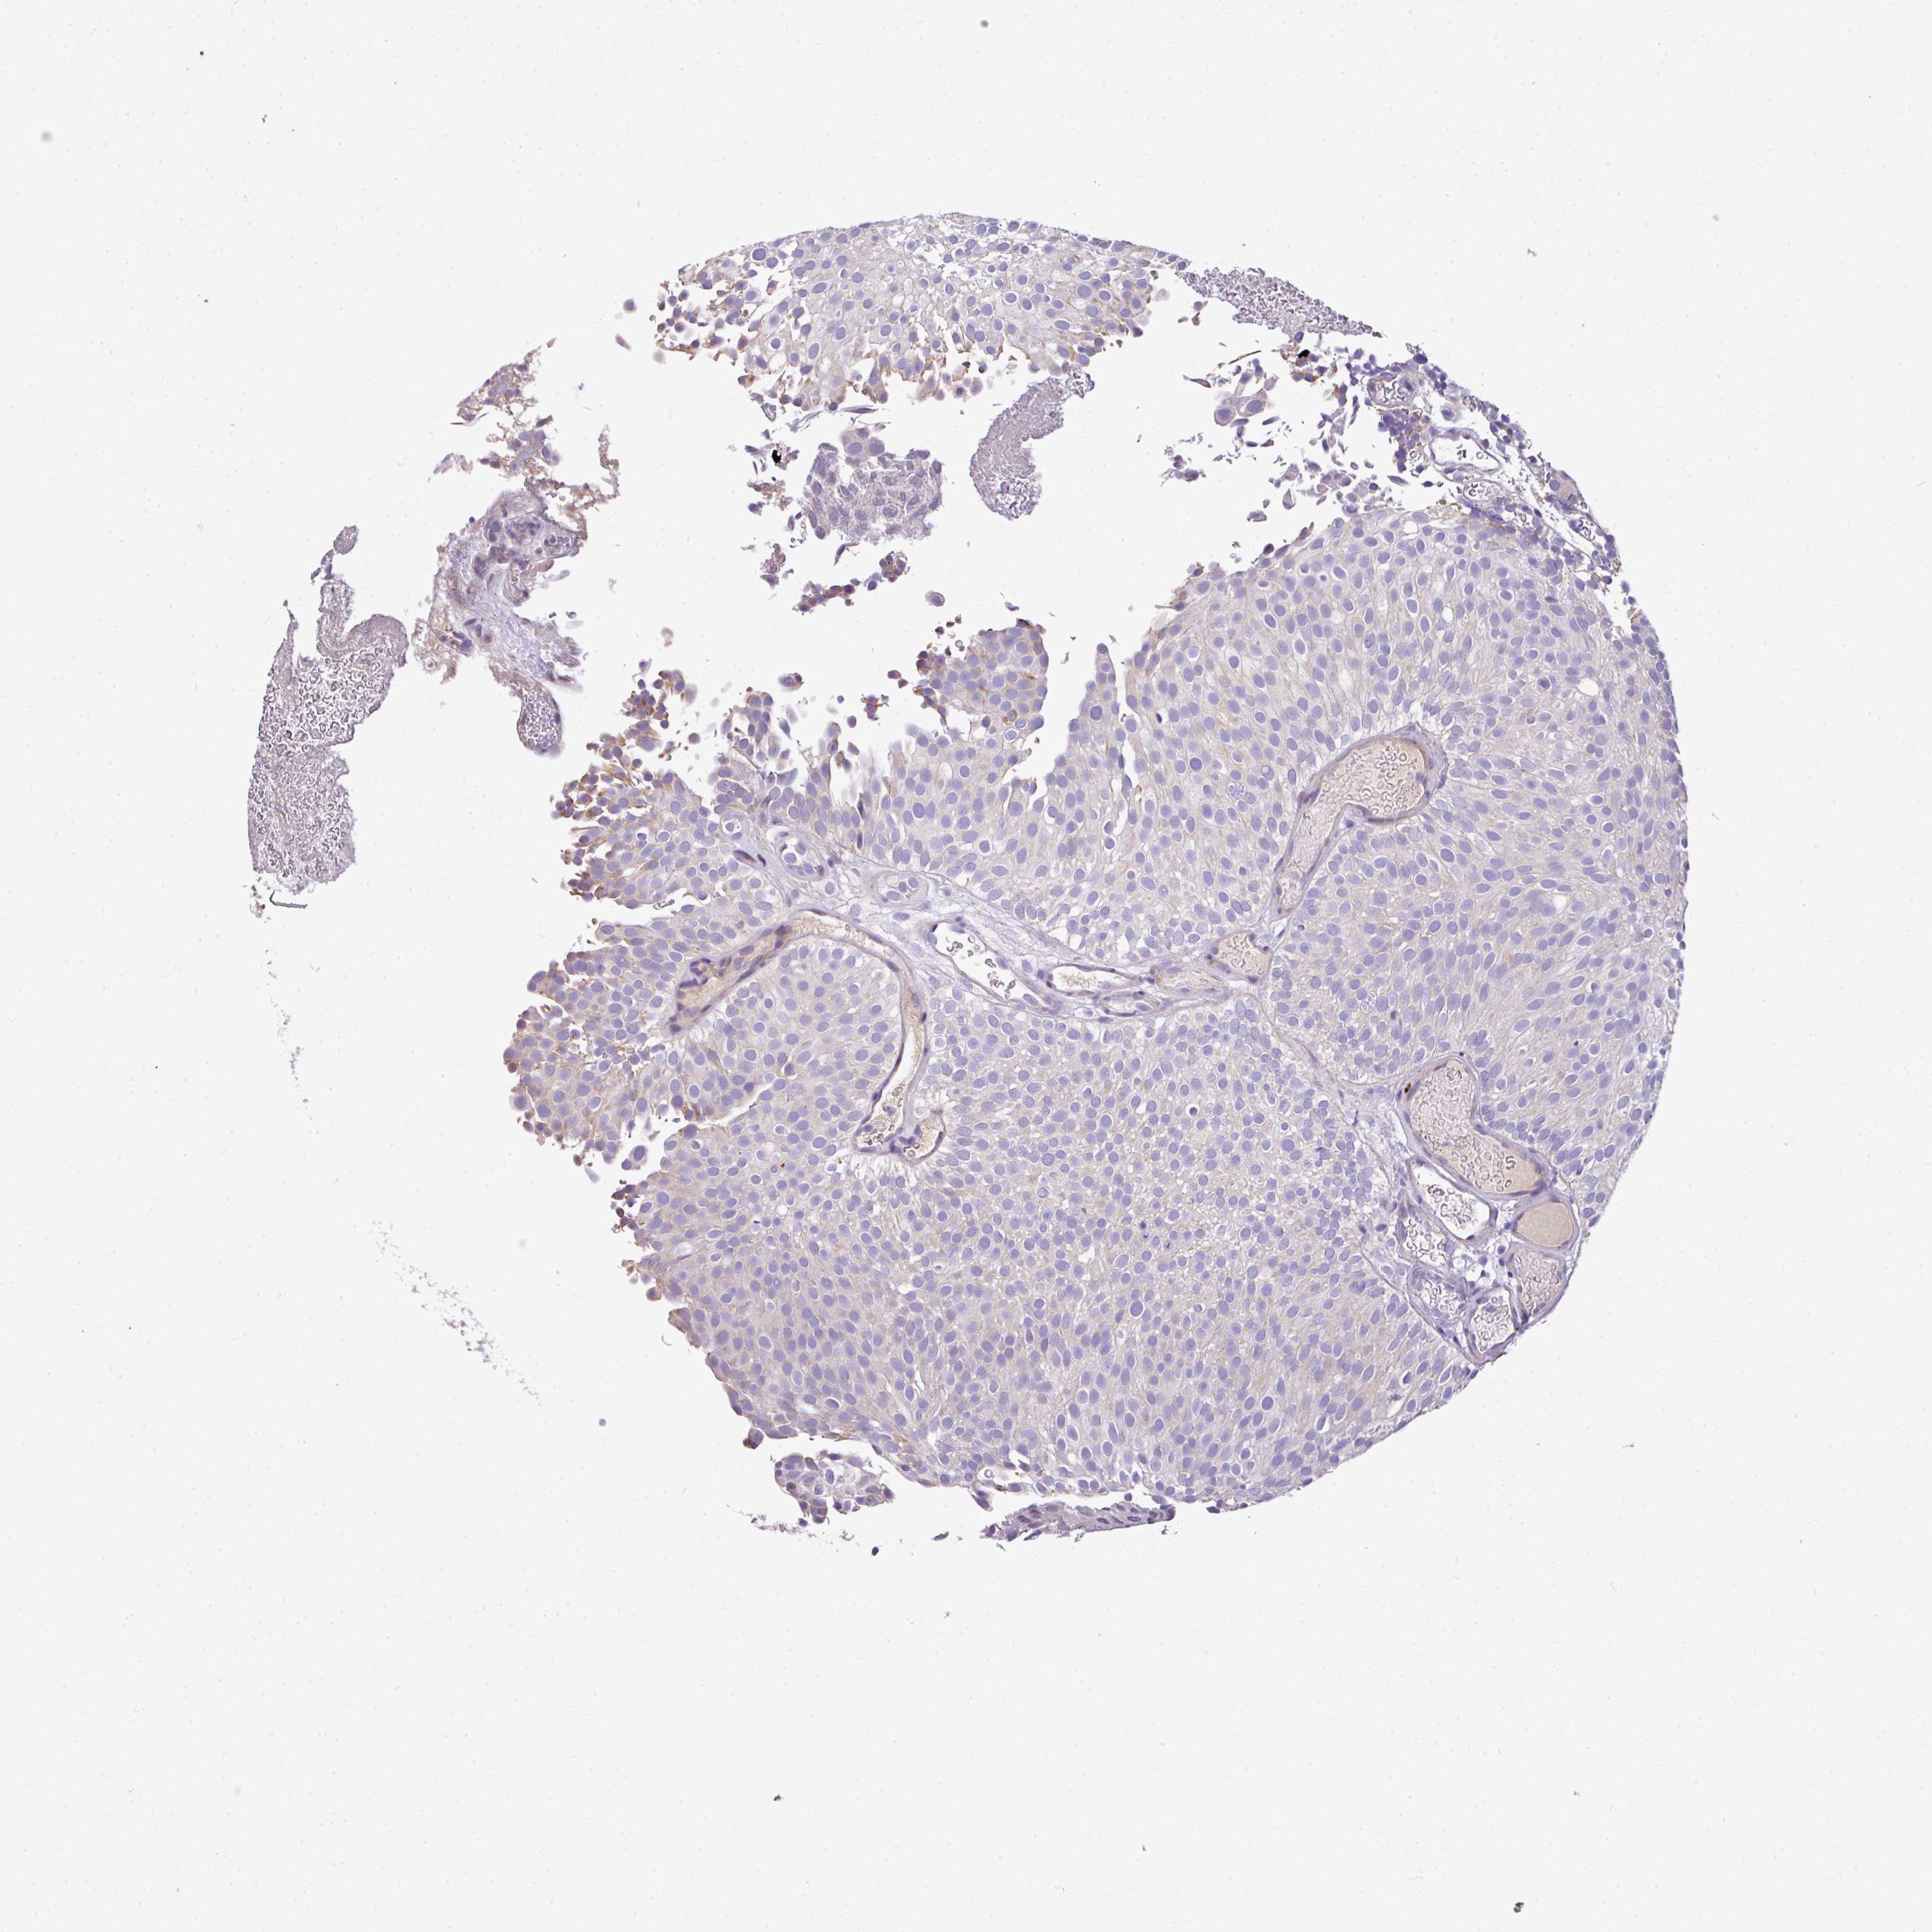

UROTHELIAL CANCER - Protein expressioni

A mouse-over function shows sample information and annotation data. Click on an image to view it in a full screen mode. Samples can be filtered based on level of antibody staining by selecting one or several of the following categories: high, medium, low and not detected. The assay and annotation is described here.

Note that samples used for immunohistochemistry by the Human Protein Atlas do not correspond to samples in the TCGA dataset.

Antibody stainingi

Antibody staining in the annotated cell types in the current human tissue is reported as not detected, low, medium, or high, based on conventional immunohistochemistry profiling in selected tissues. This score is based on the combination of the staining intensity and fraction of stained cells.

Each image is clickable and will lead to virtual microscopy that enables deeper exploration of all samples and also displays staining intensity scores, fraction scores and subcellular localization as well as patient and tissue information for each sample.

Antibody HPA051482

Staining

High

Medium

Low

Not detected

Intensity

Strong

Moderate

Weak

Negative

Quantity

>75%

75%-25%

<25%

None

Location

Urothelial carcinoma, High grade

Urothelial carcinoma, Low grade

Urothelial carcinoma, NOS